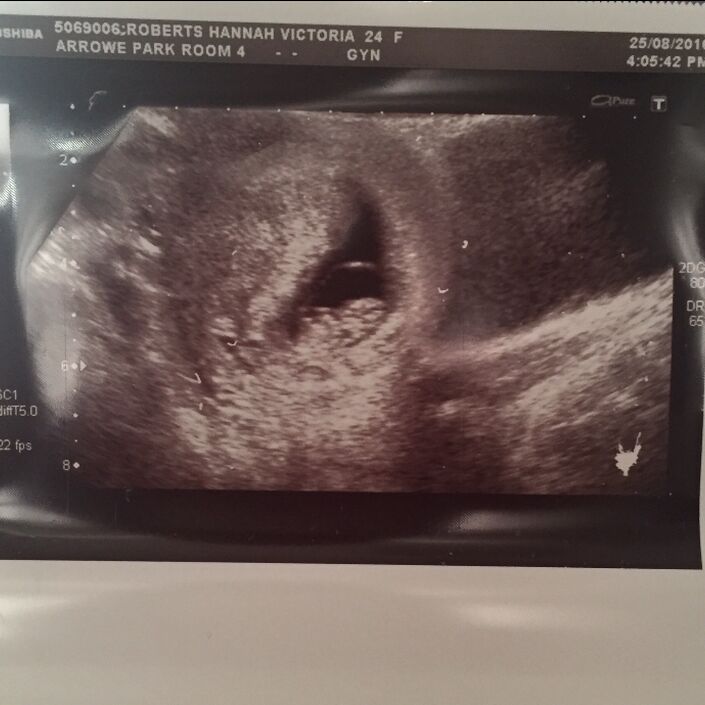

Nicki's twin sons Henry and Archie were born prematurely at 23 weeks gestation. Sadly, Archie passed away in hospital.